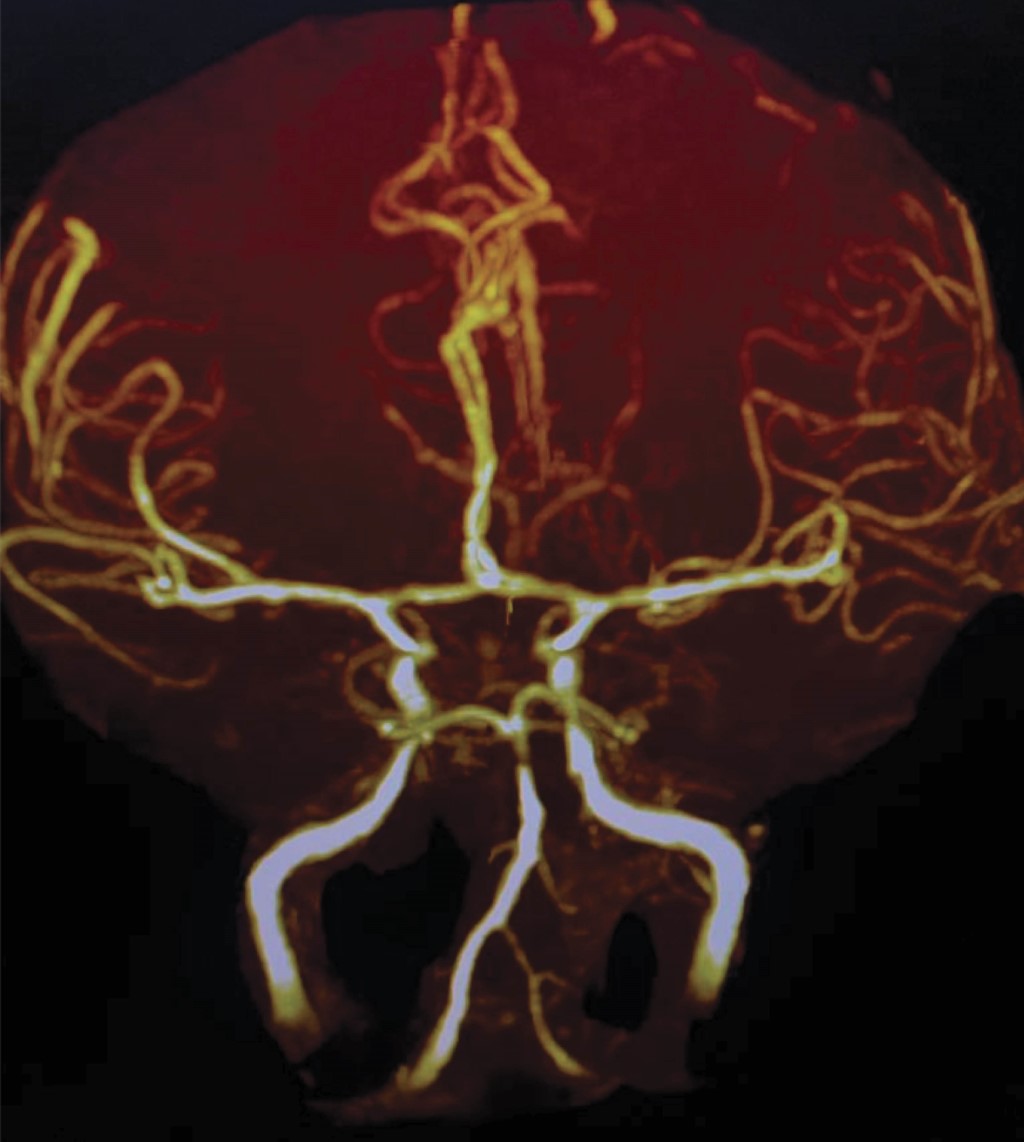

Mujer de 32 años sometida a oclusión tubárica bilateral bajo anestesia epidural en agosto de 2022. El mismo día del procedimiento presentó cefalea punzante, holocraneal, de instauración súbita, la cual fue persistente por una semana hasta que se agregó rigidez cervical, lumbalgia, náusea y vómito. A la semana refirió fotofobia y fonofobia, así como náuseas y vómitos; posteriormente, se agregó fiebre continua, no cuantificada. Decide acudir a servicio de urgencias por la alerta sanitaria, donde se tomó un citoquímico de líquido cefalorraquídeo con las siguientes características: 64 leucocitos, glucosa 34 mg, proteínas 62 mg y toma de PCR para Fusarium positiva. La paciente se trató con anfotericina B calculada a 5 mg/kg, voriconazol 300 mg y ácido acetilsalicílico 150 mg. Continuó este esquema por 18 días, agregándole alteraciones en las funciones mentales, sobre todo a nivel de la atención, la memoria reciente y la función ejecutiva. Se realiza angiorresonancia donde se encuentran datos compatibles con vasculitis de las ramas distales de ambas arterias cerebrales medias de predominio izquierdo y arrosariamiento de la arteria basilar (Figura 2). Por los hallazgos y por lumbalgia persistente se realiza imagen por resonancia magnética (IRM) de neuroeje encontrándose una aracnoiditis espinal importante a nivel de L4-L5-SI (Figura 2). Completó seis semanas de tratamiento antifúngico y esteroide sistémico, egresando por mejoría clínica y de los parámetros de líquido cefalorraquídeo.

Figura 2